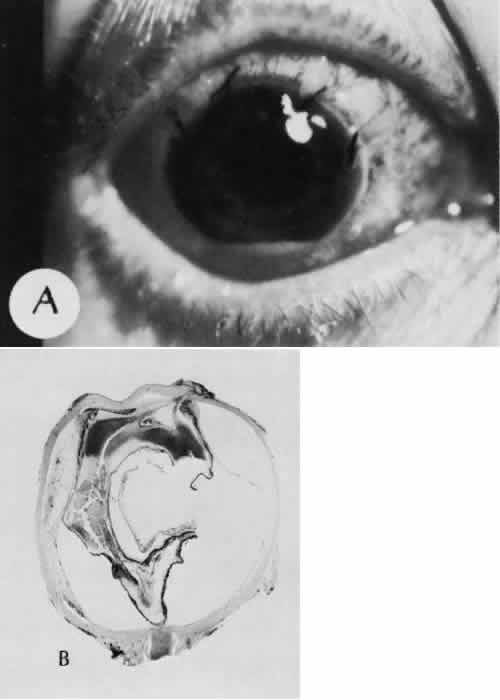

Fig. 31. A case of choroidal detachment. A. By fundus reflex, a large dome-shaped mass can be seen originating from the choroid. The differential diagnosis would include uveal malignant melanoma. In this case, the clinical findings were due to choroidal detachment from the sclera because of fluid accumulating in the suprachoroidal space following cataract surgery. B. The histologic section from another case of choroidal detachment illustrates the location (arrow) and extent of the detachment. In this case the detachment extends to the region of the ciliary body limited anteriorly by the attachment of the choroid to the scleral spur. The displacement of the ciliary body will result in apparent shallowing of the anterior chamber. (Hematoxylin-eosin stain; × 6.)

Iris or lens capsular incarceration into the wound and extending to the conjunctival space (Figs. 32 and 33) may act as a wick through which aqueous can escape, causing a flat anterior chamber. Histologically, iris, which is frequently recognized only by the presence of melanocytes, is seen in the limbal scar, in the limbal episclera, or in both areas.

Fig. 32. A case of retinal detachment. A. In this case, the iris has become incarcerated into a limbal wound. A series of events leads to total retinal detachment (morning glory detachment). The presence of multiple areas of macrocystic degeneration of the detached retina indicates that the situation is chronic and probably not repairable. B. The histologic section of this case indicates the extent of iris incarceration and the fragility of the wound. (Hematoxylin-eosin stain; × 40.)

Fig. 33. A case of iris prolapse through a limbal wound. A. A large black mass has appeared at the limbus of a patient with a history of cataract extraction. There may or may not be a history of trauma or Valsalva maneuver. The differential diagnosis at first glance would certainly include primary conjunctival malignant melanoma or extraocular extension of a primary uveal malignant melanoma. A major differential observation from iris prolapse is the character and degree of alteration of the iris tissue remaining within the eye. B. By histologic section no cellular mass is present either in the episcleral or uveal tissue. The remaining iris is stretched and adherent to the posterior corneal surface. (Hematoxylin-eosin stain; × 40.)